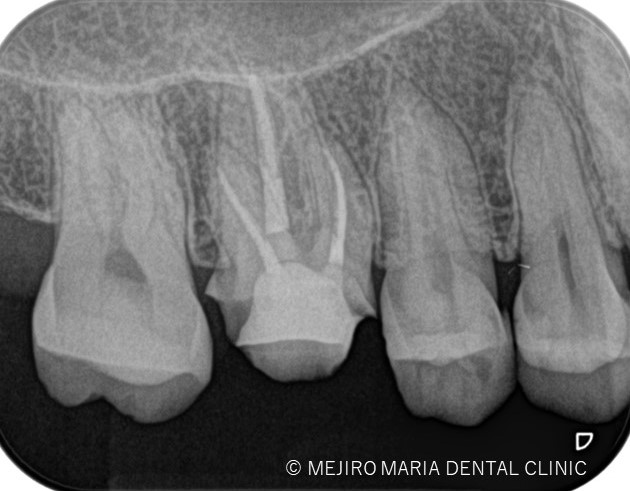

歯科用拡大鏡、歯科用顕微鏡下にて、軟化象牙質(虫歯)を除去後、歯髄を確認すると一部の歯髄には血流がなく部分壊死を起こしていることがわかる。

今回は術前に歯髄炎による疼痛を確認していたため、水酸化カルシウムを貼薬した後、2回目の治療にて根管充填、支台築造処置を終了させている。

|歯の寿命を左右する初回根管治療_術前術後のレントゲン画像比較-1024x756.jpg)